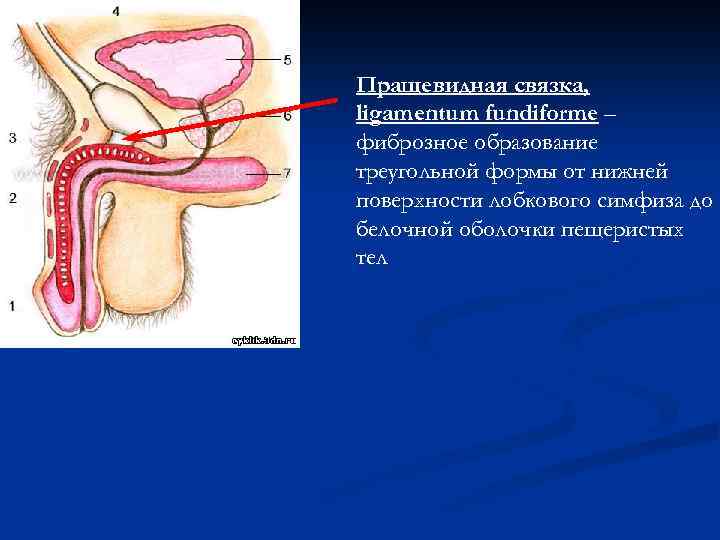

Пращевидная связка, ligamentum fundiforme – фиброзное образование треугольной формы от нижней поверхности лобкового симфиза до белочной оболочки пещеристых тел

Пращевидная связка, ligamentum fundiforme – фиброзное образование треугольной формы от нижней поверхности лобкового симфиза до белочной оболочки пещеристых тел